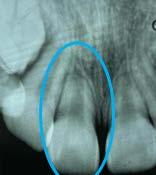

Estudios tomográficos

En el corte sagital ( Figura 8 ) se muestran las inclinaciones dentales alteradas hacia vestibular de ambos incisivos. Finalmente en una vista

axial la forma de arcos cuadrada y la malposición dental clasificada como apiñamiento leve.

Figura 8. Cortes sagital, inclinaciones dentales superior e inferior, axial tomográfico de las arcadas.